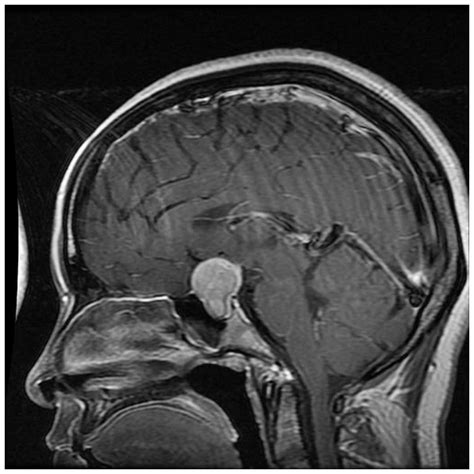

Receiving a diagnosis or a suggestion from your doctor to undergo a Pituitary Microadenoma MRI can be an anxiety-inducing experience. However, understanding what this procedure entails, why it is necessary, and what the results actually mean can significantly alleviate that stress. A pituitary microadenoma is a small, typically benign tumor located in the pituitary gland—a pea-sized structure at the base of the brain often referred to as the "master gland" because it controls many vital functions of the endocrine system. Because these growths are small (defined as less than 10 millimeters in diameter), specialized imaging is required to visualize them accurately, making the MRI the gold standard for diagnosis.

When it comes to identifying lesions under 10mm, not all imaging techniques are created equal. A standard brain MRI may sometimes miss a microadenoma. Consequently, a dedicated pituitary protocol is essential. This specialized scan focuses heavily on the sella turcica, the bony structure housing the pituitary gland.